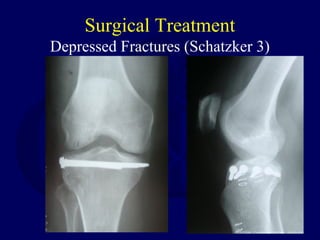

Surgical Treatment

Depressed Fractures (Schatzker 3)